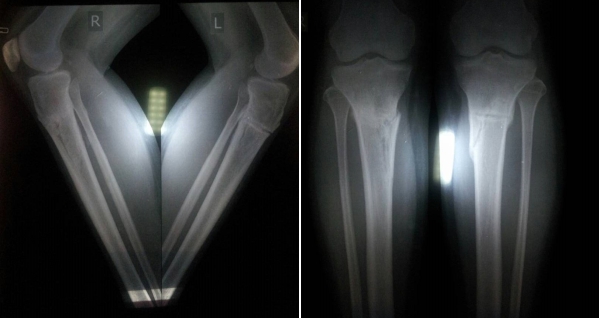

«Кармен» 50 дней с момента снятия аппаратов

50 дней с момента снятия аппаратов. Сращение отличное. Разрешено все без ограничений.